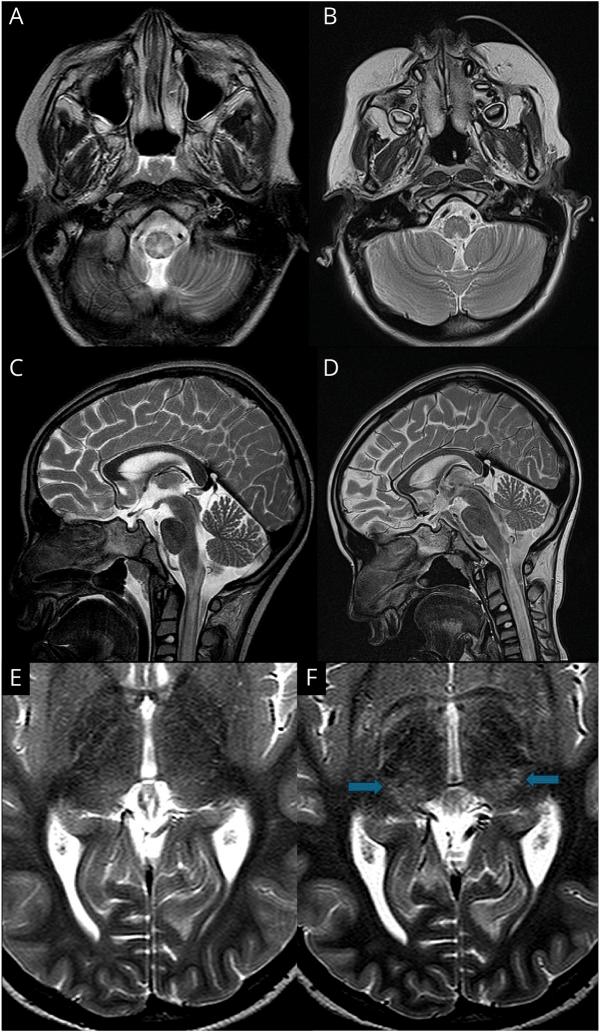

We identified and included 15 children (5 girls, 10 boys). The median age at onset was 9.9 years (range: 2-16 years). All children presented with features of AE or meningitis, acute cerebellitis, or transverse myelitis. CSF pleocytosis was common (13/15, median 245 cells/μL), and 13 (87%) of 15 harbored GFAP-abs in their CSF, 8 (53%) of whom did not have detectable GFAP-abs in their serum. MRI was abnormal in 15 (100%) of 15 children: Specific patterns included confluent lesions in the pons or caudate nucleus (11/15; 73%), peri-aqueductal regions (13/15; 87%), and spinal cord (6/10; 60%). 12 children had a favorable outcome (mRS score of </= 1). Two patients died in the acute phase or during follow-up.

我们确定并纳入了 15 名儿童(5 名女孩,10 名男孩)。发病中位年龄为 9.9 岁(范围:2-16 岁)。所有患儿均表现为 AE 或脑膜炎、急性小脑炎或横贯性脊髓炎的特征。CSF 细胞增多症常见(13/15,中位数 245 个/μL),15 名患儿中有 13 名(87%)的 CSF 中存在 GFAP-abs,其中 8 名(53%)患儿血清中未检测到 GFAP-abs。15 名患儿的 MRI 异常(100%):特定模式包括桥脑或尾状核的融合性病变(11/15;73%)、导水管周围区域(13/15;87%)和脊髓(6/10;60%)。12 名患儿预后良好(mRS 评分<=1)。2 名患儿在急性期或随访期间死亡。